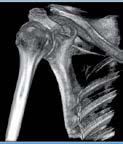

L’innovazione e la sicurezza sono due dei valori perseguiti dallo Studio Braconi a Terni, un punto di riferimento nell’ambito della radiologia 3D ortopedica grazie alla presenza del macchinario Newton 5G XL: si tratta dell’unico apparecchio nel Centro Italia che permette di eseguire una perfetta diagnostica per immagini in ortopedia e per la cervicale, oltre per le piccole articolazioni come seni paranasali, orecchie, colonna cervicale, gomito, polso, mano, ginocchio, caviglia e piede.

Nell’ambito della radiologia 3D ortopedica, il centro diagnostico utilizza il nuovissimo macchinario NewTom 5G XL, in grado di individuare con la massima precisione la presenza di fratture o lussazioni delle articolazioni, controllare la corretta guarigione di una frattura, valutare una lesione o una ferita causata da infezione, artrite o crescita anormale dell’osso.

Se con la radiologia tradizionale era necessario eseguire scansioni multiple, la novità introdotta dal macchinario NewTom 5G XL risiede nella capacità di fornire immagini ad alta risoluzione in un’unica scansione, mostrando nitidamente i dettagli delle articolazioni degli arti superiori e inferiori. Inoltre, a differenza della tecnologia 2D, la radiologia 3D ortopedica permette di individuare immediatamente alcune patologie come quella del metatarso, la quale richiede un allineamento visivo dedicato o una diagnosi delle micro fratture ossee.

Un altro valore aggiunto che rende la radiologia 3D ortopedica uno strumento fondamentale nell’ambito della diagnostica per immagini attuale è la bassissima dose di radiazioni emesse: infatti, la tecnologia CBCT garantisce una dose fino a 10 volte inferiore rispetto al MSCT.